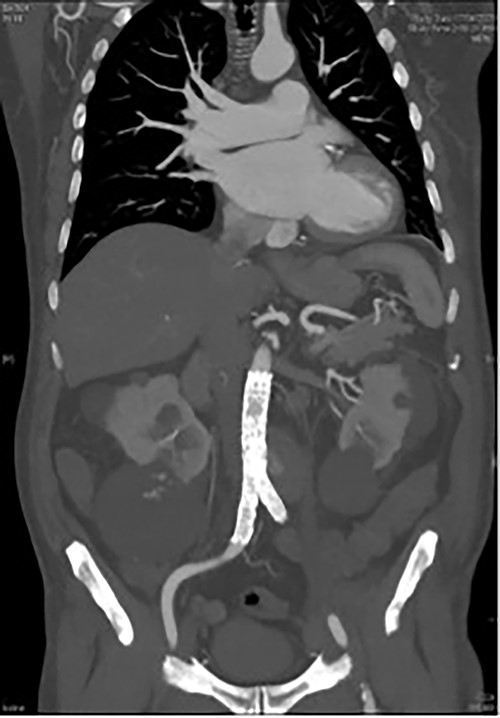

A 73-year-old male presented with a 1-week history of back pain on a background of hypertension, atrial fibrillation and bladder cancer. Computed tomography (CT) angiography demonstrated a 47 × 46 × 47 mm saccular aortic pseudoaneurysm of the infrarenal aorta with a contained rupture (Fig. 1). The patient remained hemodynamically stable with mildly elevated inflammatory markers (C-Reactive Protein (CRP), 85 mg/l, white cell count (WCC) 6.5 × 109/l). The abdominal aorta 5 months previously was normal on CT when a course of intra-vesical BCG for transitional cell carcinoma of the bladder had been ceased due to the development of fevers and syncope. Thus, Mycobacterium bovis involvement of the false aneurysm was suspected. Emergent endovascular repair was performed with a covered stent graft system successfully excluding the ruptured aneurysm sac on post-operative CT angiogram. A CT-guided fine needle aspirate of the aneurysmal sac was later conducted (Fig. 2). PCR of the aspirate returned a low-positive result confirming the diagnosis with M. bovis subsequently isolated on culture. Empirical antibiotics were ceased and he was commenced on a planned 18-month antituberculosis regimen of ethambutol, isoniazid and rifampicin guided by gene deletion analysis (GeneXpert MTB/RIF Ultra assay). Fluorodeoxyglucose-positron emission tomography (FDG-PET) scan was used to monitor the level of activity of the infection (Fig. 3). The patient was discharged home on Day 10 of admission. Aneurysm sac size was decreased at 3 and 6 months on CT angiogram and FDG-PET but there was ongoing FDG avidity around the aneurysm sac; there were no other sites of involvement. The patient remains otherwise well and has returned to his premorbid activities.

FDG PET/CT study demonstrating a rind of intense FDG uptake (SUV max 13.4) along the circumference of the lateral lower aortic aneurysm abutting the prosthesis however demonstrating no uptake tracking along the prosthesis. No other areas of FDG activity were demonstrated. (A) Coronal and (B) axial.